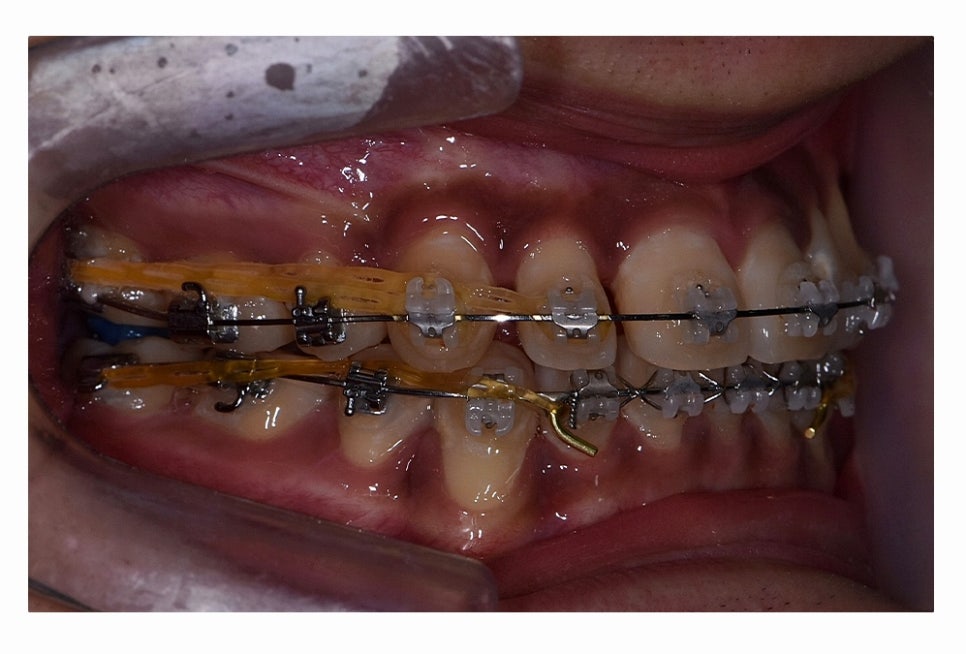

오늘 보시는 환자분의 사례처럼 덧니가 치아끼리 겹쳐 있는 경우에

치아의 이동 공간 확보를 위해서 덧니 발치 필요한 사례였으며

교합과 치아교정 후 얼굴 변화를 고려할 때도 치아교정 과정에서

발치가 필요한 사례였다고 볼 수 있어요.